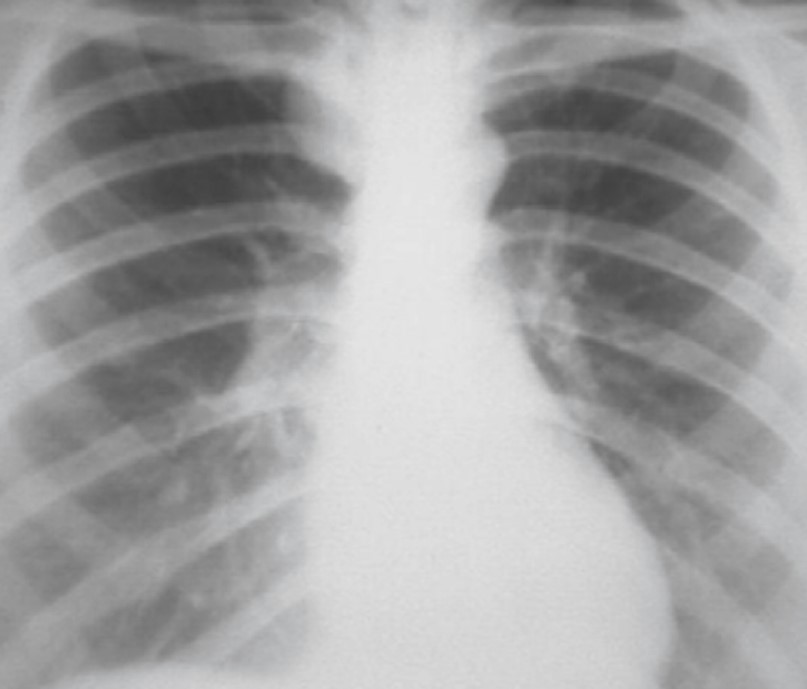

На рентгенограммах внутрибронхиальная липома проявляется весьма характерными признаками – ​спадением доли легкого вследствие обтурации соответствующего бронха. Чаще всего липомы локализуются в крупных бронхах – ​в долевом либо сегментарном. Диагноз липомы гистологически можно подтвердить после бронхоскопии, биопсии опухоли и тканевого исследования [34, 35]. Так, на рентгенограммах липома зачастую неотличима от центрального рака легкого (рис. 28-30).

Рис. 28. Гистологически подтвержденная липома бронха